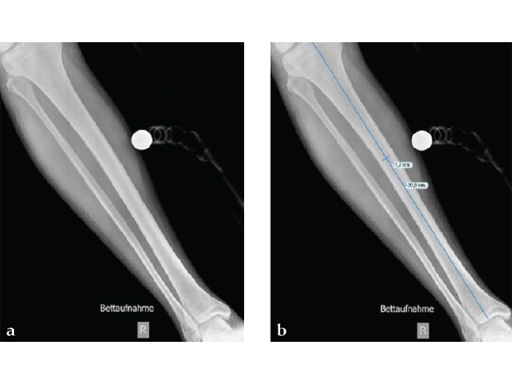

The mechanical properties of the nail are not affected by the coating. Tests on human specimens and plastic bones proved the coating to be resistant to the abrasive forces present during insertion into a narrow and moist bone canal. The surgical technique does not differ from the regular standard of care in ETN implantation.